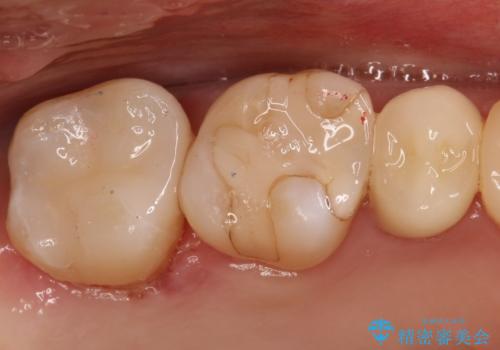

【セラミックインレー】虫歯の治療

- 虫歯を認めたため、セラミックインレーにて治療を行いました。

見た目も綺麗に修復することができ患者様には満足していただきました。

セラミックインレーの接着には必ずラバーダム防湿を行なっています。